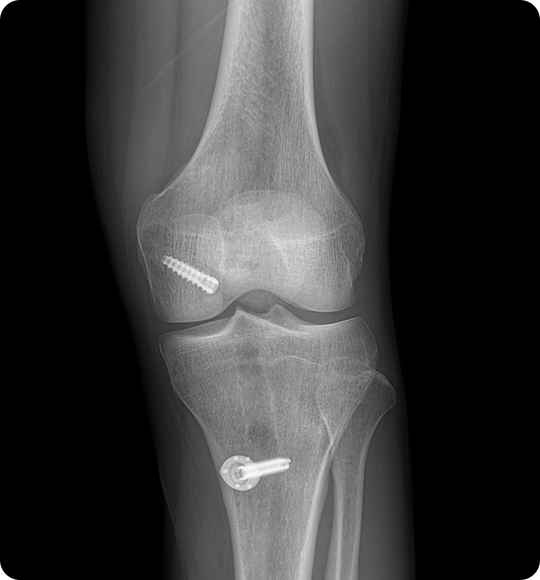

이 수술은 끊어진 인대를 봉합하는 것이 아니라

자가건(햄스트링건, 슬개건 등) 또는

인공건을 이용해 새로운 인대를 이식하게 되며,

재건을 통해 통증을 줄이고 무릎 기능을 되살립니다.

인대를 뼈에 단단히 고정 후,

관절 내 위치와 장력을

확인하고 봉합합니다.